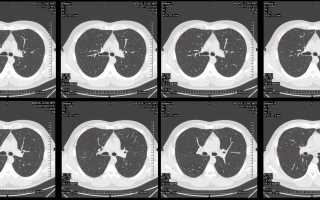

Компьютерная томография (КТ) грудной клетки — важный инструмент медицинской диагностики, позволяющий получать детализированные изображения органов и тканей грудной области. Методика полезна для выявления заболеваний, таких как опухоли, воспалительные процессы, травмы и патологии легких и сердца. В статье рассмотрим показания к проведению КТ грудной клетки, преимущества и ограничения метода, а также его роль в диагностическом процессе, что поможет читателям понять значимость и эффективность КТ в медицине.

КТ грудной клетки является важным диагностическим методом для выявления различных заболеваний органов грудной полости. Специалисты подчеркивают, что благодаря высокой разрешающей способности КТ можно получить детализированные изображения легких, плевры, сердца, сосудов и других структур. Это позволяет с высокой точностью выявлять опухоли, воспалительные процессы, травмы и другие патологии. Кроме того, КТ грудной клетки дает возможность проводить гидродинамические и функциональные исследования, что делает его незаменимым инструментом в диагностике и мониторинге состояния пациентов с заболеваниями грудной полости.

Важная часть компьютерной томографии — КТ грудной клетки. Львиную долю назначений данной диагностики занимает поиск пневмонии, в частности, в 2020-2021 году — поиск пневмонии, возникшей в результате развития в организме коронавирусной инфекции.

можно выявить очаги воспаления на самой начальной стадии, и, соответственно, вовремя назначить лечение. На сканах будут видны очаги воспаления размером от миллиметра. Также назначают эту диагностику и через год после тяжелой пневмонии, чтобы убедиться, что не развился легочный фиброз.